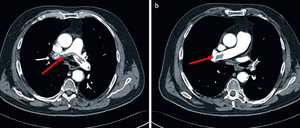

Das griechische Wort „embolos“ bedeutet so viel wie: hineingeschoben. Es bezeichnet einen kleinen Pfropf – der lebensgefährlich werden kann. Wie im Fall von Philipp Mißfelder, der in der Nacht zu Montag an einer Lungenembolie starb.